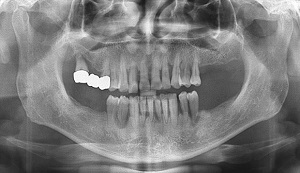

- 초기 뚜렷한 증상 없어, 통증과 흔들림이 나타나는 단계 이미 상당히 진행된 뒤, 주기적 정기검진 필수 - 치주염의 원인 잘못된 칫솔질, 치주포켓 닦는 ‘바스법’ 실천 통해 올바른 양치질 습관 가지는 것 중요해 전국 곳곳 초겨울 추위가 찾아왔다. 찬바람 부는 겨울철이 되면 이가 시리다며 치과를 찾는 사람들이 많아지는데 계절에 상관없이 이가 시리다는 것은 치아나 잇몸에 문제가 있다는 신호다. 보통 시린 이는 무심코 방치하는 경우가 많다. 증상이 지속되지 않고 생활에 크게 지장이 있을 만큼 통증이 심하지 않은 데다 겉으로 봤을 때 치아가 많이 상했다고 생각하지 않아 ‘이러다 괜찮아지겠지’하는 생각으로 대수롭지 않게 넘기는 경우가 많기 때문. 하지만 시린 치아는 치주염의 전조증상일 수 있는 만큼 정확한 원인을 파악해 미리 예방할 수 있어야 한다. 충치는 해당 치아만 치료하거나 발치하는데 그치지만 치주염은 염증으로 진행되면서 잇몸뼈라고 불리는 치조골을 광범위하게 녹인다. 한 번에 여러 개의 치아를 뽑는 경우가 흔하다는 데에 심각성이 있다. 일산사과나무치과병원 김혜성 대표원장은 “치아는 잇몸과 치조골, 치주인대 등이 치아의 뿌리부터 단단히 잡고 있는 형태인데 잇몸이나 잇몸뼈에 염증이 생기면 통증이나 큰 증상 없이 치아 주변을 조금씩 녹여나가게 된다. 통증과 흔들림이 나타나는 단계는 치주염이 이미 상당히 진행된 뒤이기 때문에 특히 30대 이후라면 치아와 잇몸의 작은 변화에도 민감하게 반응할 필요가 있다”며 “유전적으로 치주염에 취약한 사람도 있지만 당뇨, 임신, 흡연, 스트레스 등은 특히 주의해야 하는데 염증의 원인이 되는 치태와 치석을 완전히 제거하기 힘들기 때문에 주기적으로 정기 검진과 함께 스케일링을 받는 것이 좋다”고 말했다. 치주염의 원인은 다양하지만 가장 주된 원인을 꼽으라면 잘못된 칫솔질을 들 수 있다. 염증을 일으키는 주된 원인은 입속 세균인데 치태 1g에는 약 1억 마리의 세균이 살고 있다. 이를 제대로 제거하지 않으면 치주염으로 발전하고 제때 치료받지 않으면 잇몸과 치조골을 녹이게 되는 것이다. 치주염을 예방하고 치료하려면 ‘바스법’으로 ‘치주포켓’이라 불리는 세균 주머니를 잘 닦아주는 것이 매우 중요하다. 치주포켓은 잇몸과 치아의 경계에 있는 주머니 모양의 틈을 말하는데 건강한 잇몸은 1~2mm 정도의 틈이지만 잇몸병이 있는 사람은 그 틈이 더 깊다. 바스법은 칫솔모의 끝을 치아와 잇몸이 닿는 부위에 45도 방향으로 밀착시켜 약 10초쯤 앞뒤 방향으로 진동을 준 뒤 옆으로 이동하는 방식이다. 치주포켓에 칫솔의 솔을 넣고 가볍게 흔들어 주고 칫솔모가 치주 포켓에 들어가서 닦아낼 수 있게 진동을 주는 것이 핵심이다. 바스법은 미국 뉴올리언스 툴란 대학 의대 학장을 역임한 바스 교수가 잇몸병을 예방하기 위해 만든 칫솔법인데, 이와 잇몸 사이에 낀 프라그가 효과적으로 제거되고 잇몸 마사지 효과까지 있어 대한치주과학회에서도 추천하는 방식이다. 김원장은 “나이가 든 어르신들의 경우 치아가 마모되거나 잇몸이 내려간 경우도 많아 치아가 시린 증상을 자주 호소하게 되는데 마모된 경우에는 더 진행되는 것을 막기 위해 마모된 부분을 수복해주는 치료를 하는 것이 좋다”며 “몇 년 전부터 치주 질환이 뇌혈관 질환은 물론, 치매에도 영향을 미친다는 연구들이 우리나라를 비롯해 여러 나라에서 보고되고 있는 만큼 평소 올바른 양치질 습관을 가지는 것이 중요하고 정기 검진을 통해 초기에 치주염을 예방할 수 있도록 노력해야 한다”고 조언했다. ※ 사과나무치과병원에서 제안하는 치주질환 자가 진단 리스트 (1개 이상 해당 될 경우 검진 필요) - 가끔씩 잇몸에서 피가 난다 - 피곤하거나 과음한 다음 날이면 이가 솟아있는 느낌이 든다 - 단단한 음식을 마음 놓고 씹을 수가 없다 - 씹을 때 아프다 - 이가 흔들린다 - 가지런하던 이가 벌어지거나 틀어진다 | |||||||||